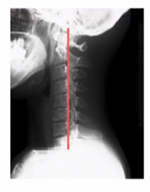

ストレートネックになる原因

ストレートネックはデスクワークなどで多く頭が前に出ることにより発生します。

アタマが前に出ると首への負荷が高まり、筋の緊張はドンドンドンドン高まっていきます。

当然、デスクワークなどは首だけの問題ではなく、姿勢の問題も大きく関与してきます。